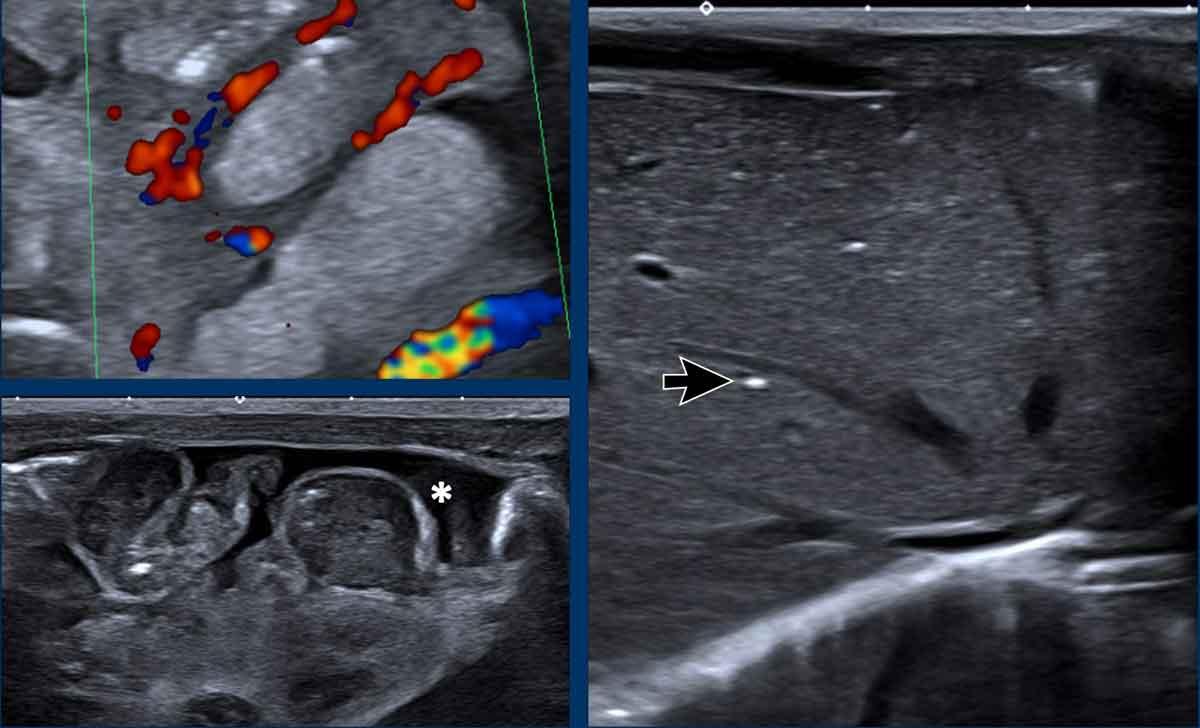

Siêu âm

Siêu âm không chỉ tập trung vào ruột mà còn cần đánh giá sự hiện diện của dịch tự do (*) và khí trong hệ thống tĩnh mạch cửa (mũi tên).

X-quang bụng âm tính không loại trừ được khí trong tĩnh mạch cửa hoặc khí trong thành ruột.